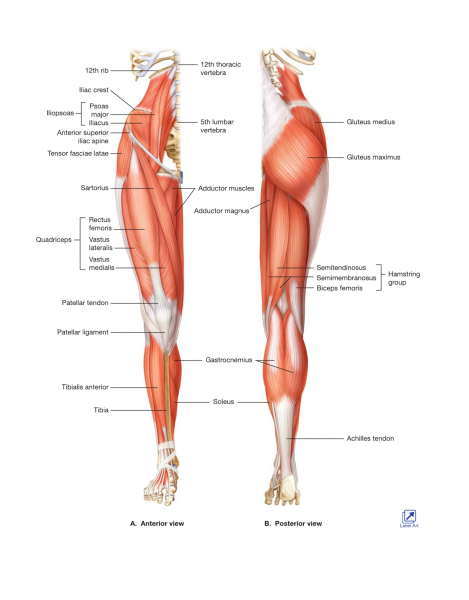

- In this next example, a person presents to the clinic with a chronic knee problem. This person has again seen many different practitioners with little or no help. The focus of treatment has been the knee. Again in this case the knee pain may be only a symptom of problem somewhere else such as the foot or the hip. If we look at the diagram below, we can see the intimate relationship between the hip, knee and foot. There can be chronic tightness in the foot or hip, biomechanical dysfunction in how the foot or the hip moves or simply a lack of stability in the foot or hip due to injury or overuse. The foot or hip dysfunction can then lead to the knee having to work a lot harder which can than result in chronic pain. In this case the foot or hip would need to be treated along with the knee to resolve the chronic knee problem.